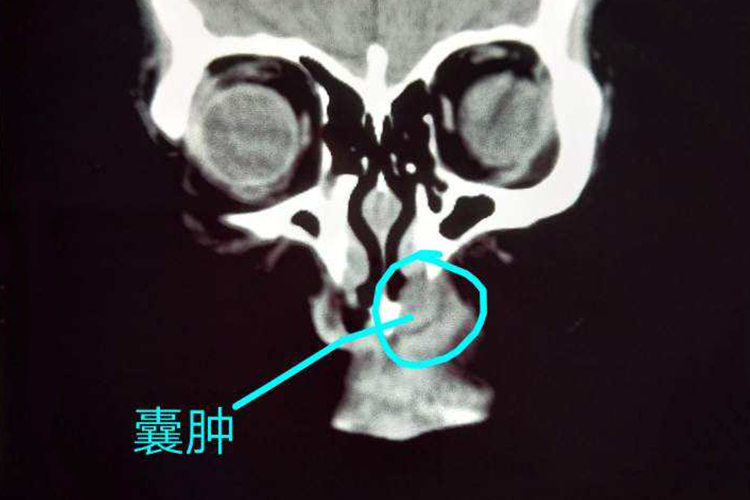

鼻前庭囊肿

囊肿发展缓慢,常单侧发病。早期囊肿小的时候无任何自觉症状。囊肿长大后,使一侧鼻前庭和鼻翼附着处隆起,伴鼻前庭部及上唇胀痛感,咀嚼时明显。囊肿较大阻塞鼻前庭时,可有同侧鼻塞。一些患者可有上颌部或额部反射性疼痛。若囊肿发生感染,可迅速增大,局部疼痛加重。